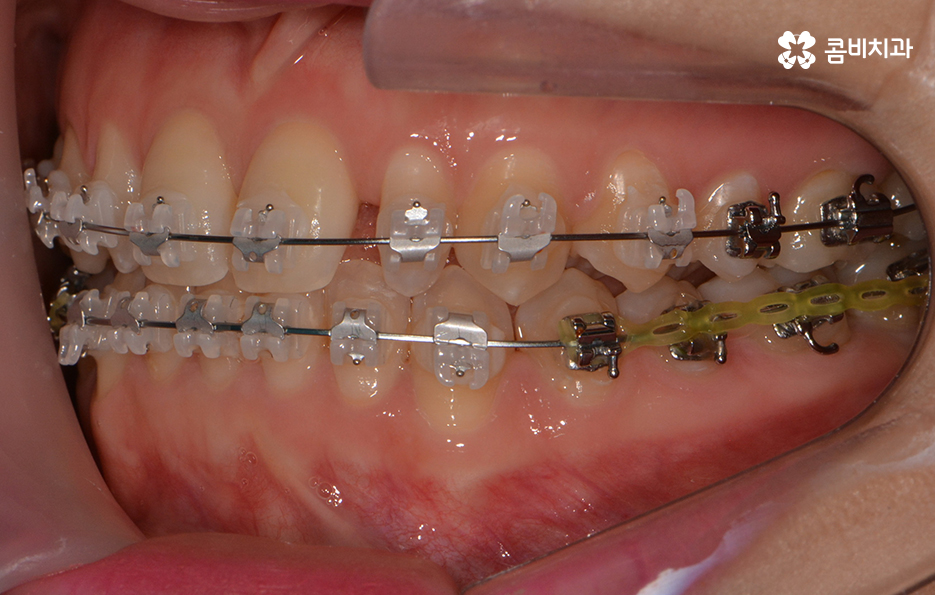

옆모습을 볼 때 치아 사이가 유독 벌어져 보이는데 심미적으로도

부담감을 느끼실 수 있지만 음식물이 치아 사이에 낀다거나

치아의 벌어짐으로 인해 치열이 반듯하게 자라지 못하기도 합니다.

전체적인 치열 상태가 비교적 가지런한 편이었기 때문에

약 1년 정도 클리피씨교정을 통해서 치열과 교합 개선이 진행 되었습니다.